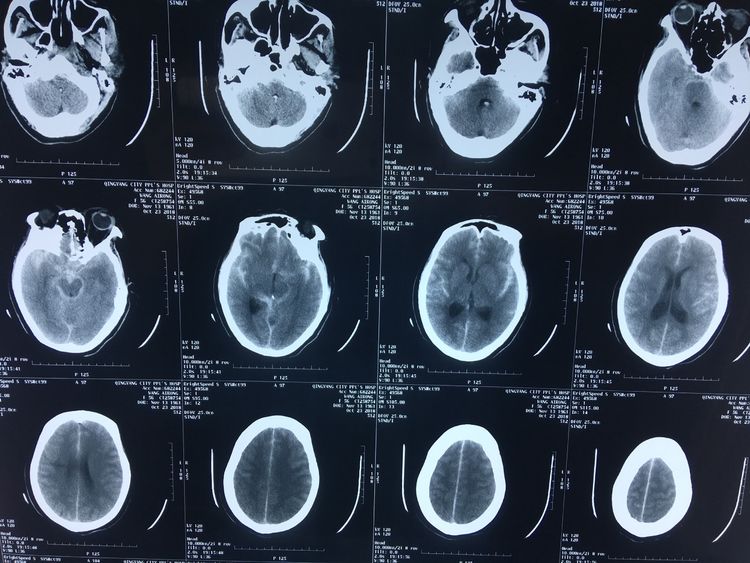

患者,女52歲,突發(fā)頭痛頭暈伴惡心到市人民醫(yī)院就診,CT提示珠網(wǎng)膜下腔出血,隨收住神經(jīng)外科。急診在我院神經(jīng)外科介入室行全腦血管造影,發(fā)現(xiàn)左側頸內(nèi)動脈后交通段一大小約23mmx17mm巨大動脈瘤。右側大腦前動脈未見顯示,供血區(qū)由左側大腦前動脈代償供血,后循環(huán)系統(tǒng)右側椎動脈優(yōu)勢供血。